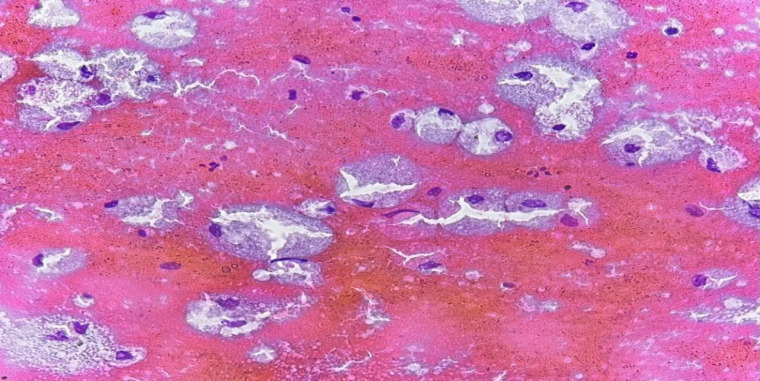

Abstract Image